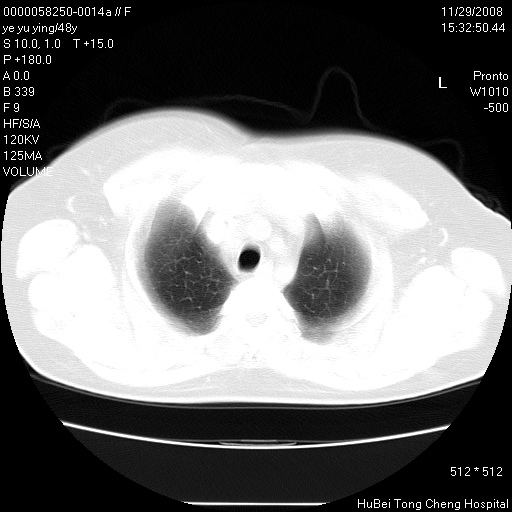

以下是引用zsl6918在2008-11-29 21:47:00的发言:[br]恶性肿瘤病史,转移瘤首先考虑。脂肪肝,胆囊结石。

以下是引用huenhao在2008-11-29 22:11:00的发言:[br]脂肪肝,胆囊结石。左肺病灶建议定期复查。

以下是引用liuyue在2008-11-30 5:44:00的发言:[br]1.左肺病变,首先考虑感染性病变,转移待排;建议治疗后复查。[br]2.肝脏密度普遍减低,考虑与化疗有关。[br]3.胆囊结石.